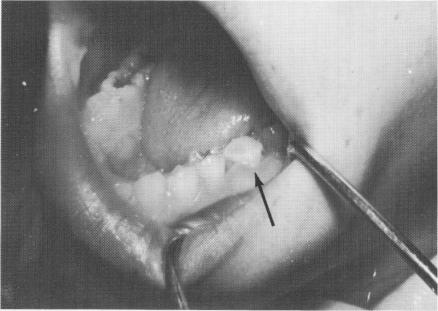

Fig. 8-72. The implant shaft is notched for retention of the acrylic core to the roughened surface of the lingual portion of the molar tooth and an acrylic core is built.

In this case, an unusual approach was taken to prevent good neighboring teeth from being sacrificed for full crown restorations. A 13-year-old girl had sagittally fractured a 6-year mandibular molar exactly in half vertically downward to the apices of the roots in a mesiodistal direction. The canals were also severed exactly in half, so that root canal therapy was impossible. The buccal half of the tooth was removed (Fig. 8-70), and a vent-plant was screwed through the bone remaining between the mesiobuccal and distobuccal roots (Fig. 8-71). The protruding shaft of the implant and the lingual half of the molar tooth were notched and locked together with acrylic (Fig. 8-72). The acrylic was prepared (Fig. 8-73) and an impression taken for a full crown gold veneer, which was cemented in position with hard cement (Fig. 8-74). A radio-